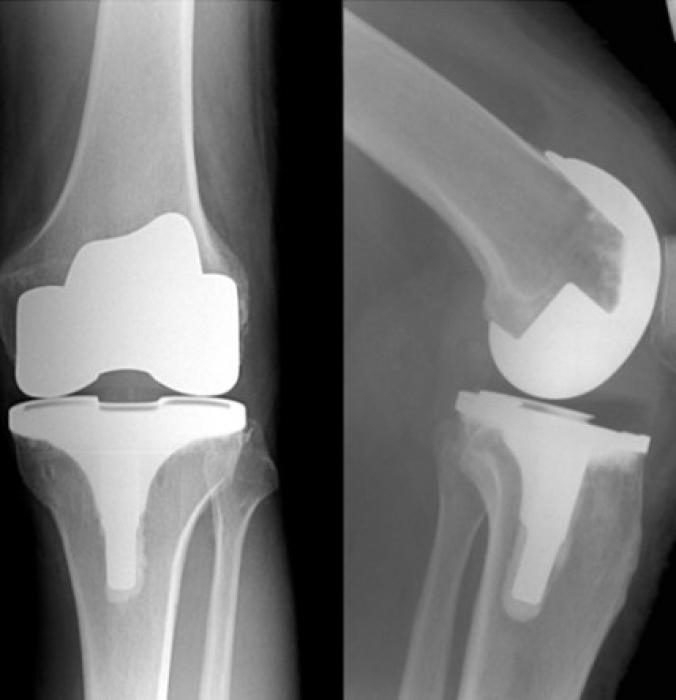

How Long Should An Artificial Knee Last . how long does an artificial knee last? An artificial knee, like the joint it replaces, can undergo damage from wear and tear. how long does an artificial knee last? You may need a knee replacement. knee replacement surgery is a surgery to replace parts of your knee joint with new, artificial parts. the question of how long does a knee replacement last is frequently asked by patients, and to date, we have not had a. joint replacement surgery is a safe and effective procedure to relieve pain, correct leg deformity, and help you resume normal activities. Research from 2019 showed that approximately 82% of total knee replacements were still functioning and doing well at 25 years. how long you stay in the hospital after surgery depends on your individual needs. the components combine to form an artificial joint that is biologically compatible and mimics the movement of your natural knee.